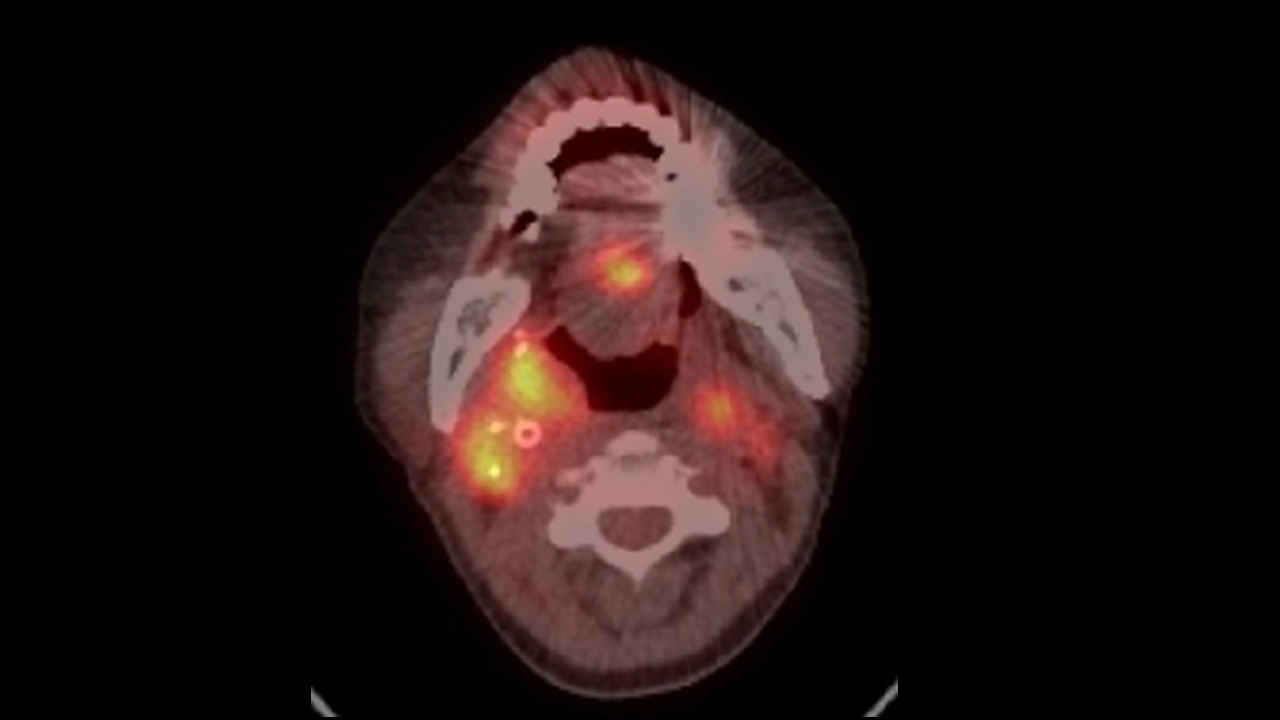

頭頸癌患者在接受標靶治療後,再接續免疫療法時,常常無法達到預期療效。研究團隊深入解析後揭露了一個關鍵原因:長期標靶治療帶來的「治療壓力」會讓癌細胞提高警覺,加速重塑腫瘤微環境,甚至主動關閉原本用來啟動免疫細胞的訊息通路,讓免疫療法失去效果。

造成癌細胞「抗壓性」的核心機制在於,當腫瘤長期受到標靶藥物壓制時,會分泌大量發炎因子 TNF-α,進而干擾 STAT1—這個原本負責啟動干擾素抗腫瘤基因的關鍵因子,形成所謂的「干擾素疲乏」(IFN-γ fatigue),讓免疫細胞對癌細胞的攻擊能力逐漸喪失。本論文的成果發表於 《Cell Reports Medicine》。